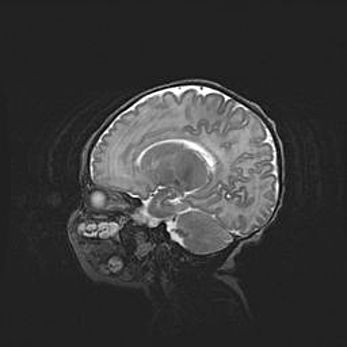

Мальформация Денди-Уокера. Киста задней черепной ямки.

Агенезия мозолистого тела.

Возраст: 2,5 месяца

Вес: 2420 г

Пол: женский

Окружность головы: 37 см

Срок гестации: 32 недели

Мальформация Денди—Уокера — редкий вид патологии ЦНС, представляющий собой врожденный порок развития каудального отдела ствола и червя мозжечка, ведущий к неполному раскрытию срединной (Мажанди) и латеральных (Лушка) апертур IV желудочка мозга. Для этогно синдрома характерна триада симптомов: гипотрофия червя мозжечка и/или полушарий мозжечка, кисты задней черепной ямки, гидроцефалия различной степени. В 70% случаев порок сочетается и с другими аномалиями головного мозга, в частности с агенезией мозолистого тела.